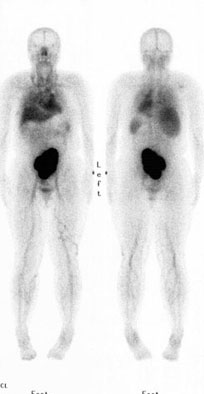

- 追加の画像は腎スキャン(Tc-99m

DMSA)での全身スキャン(右図)です。